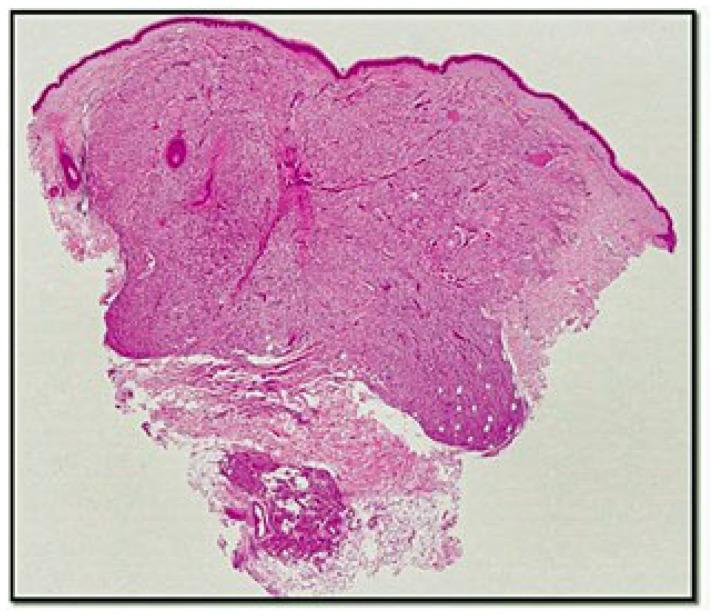

Perivascular epithelioid cell tumours (PEComas) are a growing family of tumours composed of histologically and immunohistochemically distinctive perivascular epithelioid cells. Cutaneous primitive PEComas (cPEComas) are very rare, with 65 cases described in the English literature, and occur as a painless lesion predominantly in female patients, with a wide age range. We present a new case of cPEComa found on the left thigh of a 53-year-old patient with histopathological, immunohistochemical, and molecular information. The lesion was positive for HMB-45 and focal for smooth muscle actin and desmin but negative for melan-A, S-100 protein, CD31, and CD34. Next generation sequencing (NGS) analysis demonstrated the presence of genomic aberration for baculoviral IAP repeats containing BIRC3 splice site 1622-27_1631del37. Although there are little molecular data regarding this entity, our case adds to this knowledge, considering the importance of detecting genomic aberrations in the context of specific therapies such as mTOR inhibitors.